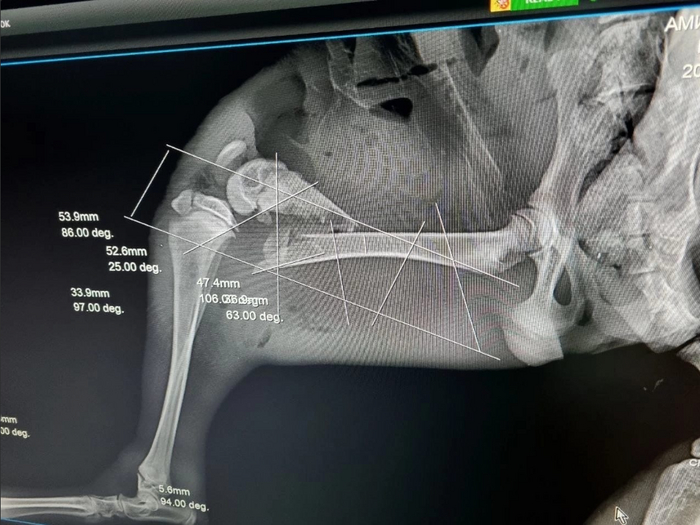

То есть лис умудрился, залезая на клетку, умудрился зацепиться задней лапой и неудачно упасть, сломав заднюю лапу со смещением.

Тут мы впервые увидели травму и "слегка" охренели. Особенно с пониманием того, что бедному зверю предположительно предстояло ждать опадания опухоли еще почти неделю

Фото пострадавшего прилагаю.

Дальше чувствительным лучше не смотреть, фото обработки ран перекисью (видно насколько правая лапа раздулась в сравнении с левой)